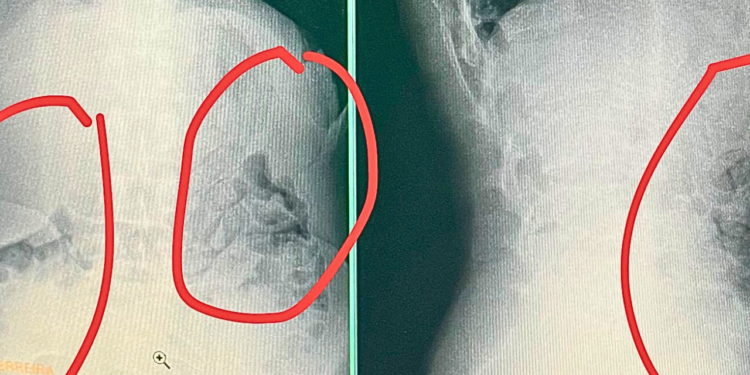

Os suspeitos foram levados para o setor de segurança do presídio e, em seguida, ao Hospital Regional, onde exames de raio-X confirmaram que cinco deles haviam engolido invólucros com o mesmo formato dos tabletes apreendidos.